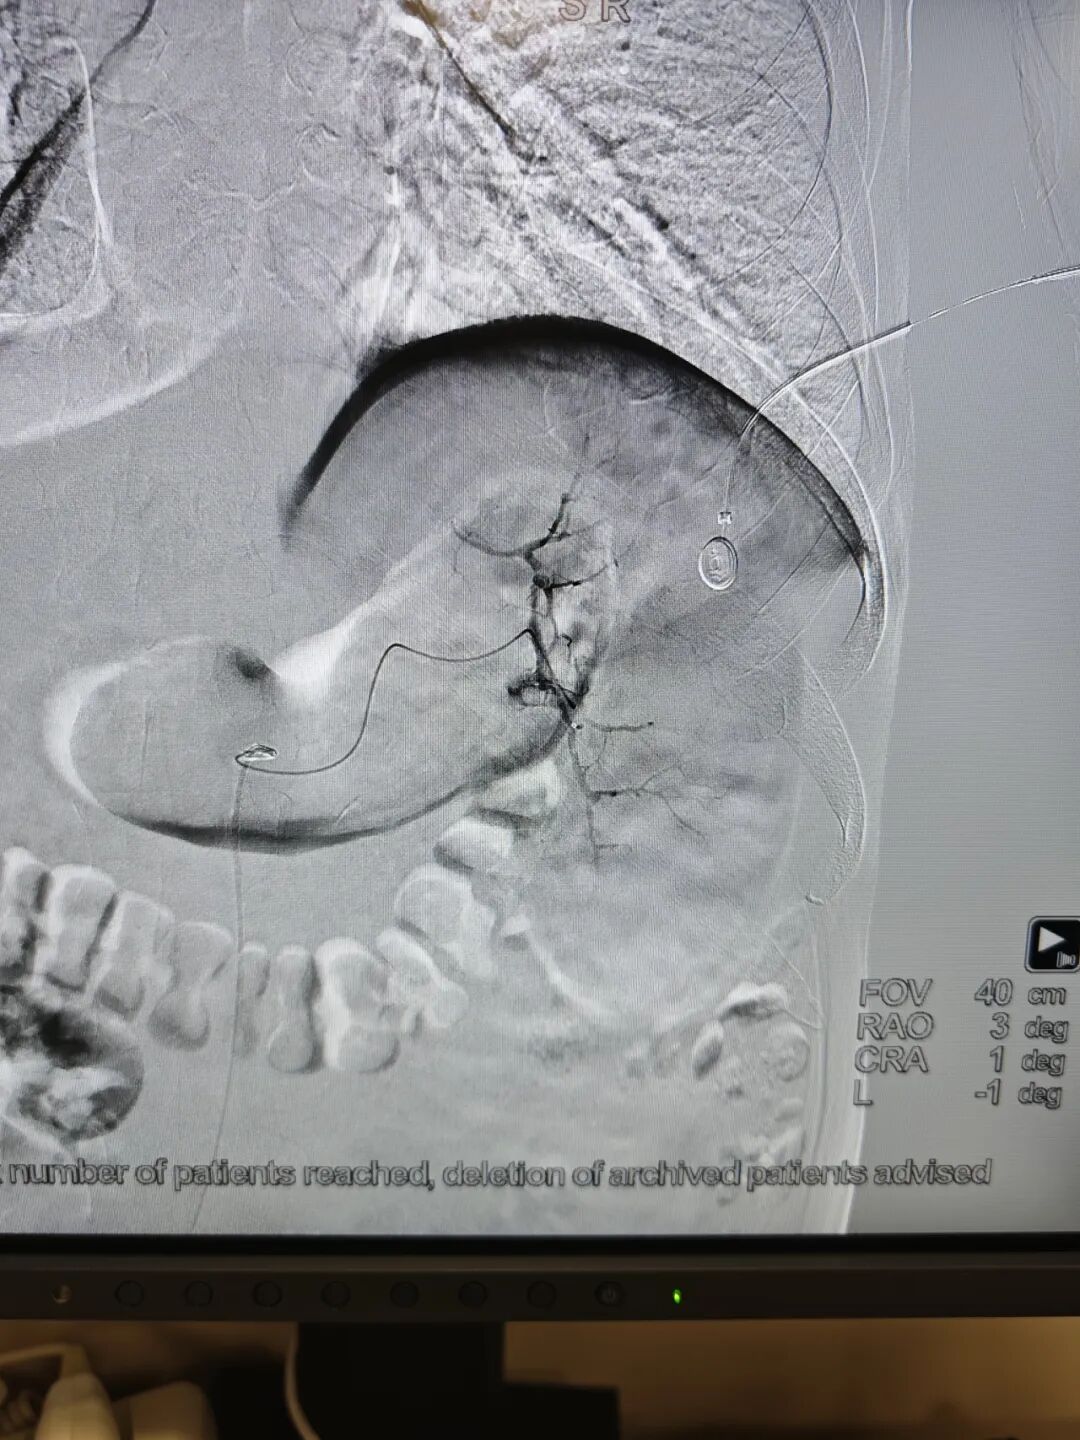

手术全程在数字减影血管造影(DSA)高清影像实时监控下开展,全程可视化操作,精准、安全、可控。

术中,介入医学科负责人卜高峰通过微细导管沿血管通路精准送达脾动脉主干,精准定位异常增生、过度亢进的病变脾组织血管分支,注入专用栓塞颗粒,选择性阻断脾脏病变区域血供,让亢进的脾组织逐步缺血萎缩,从根源解决脾功能亢进问题。

手术中,导管精准抵达脾动脉位置,清晰显示脾脏血管供血形态,为后续栓塞操作提供精准定位

栓塞过程中,通过导管向病变脾组织血管注入栓塞颗粒,精准阻断异常供血,最大程度保留正常脾组织。